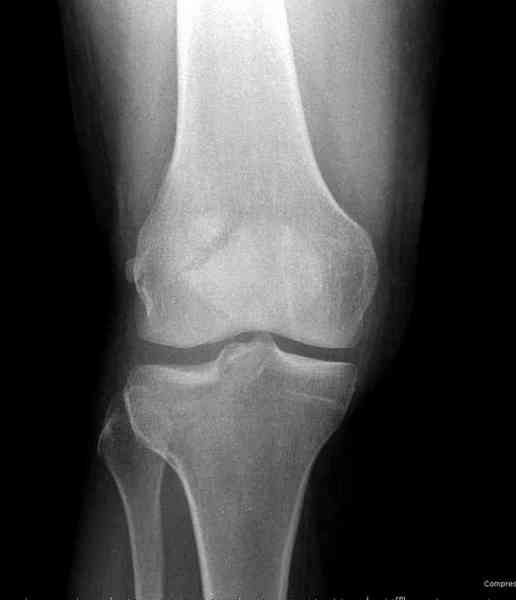

Вложение не в текстовом формате было извлечено…

Имя     : 4 lat tib plateau CT.jpg

Тип     : image/jpeg

Размер  : 50105 байтов

Описание: отсутствует

Url     : http://weborto.net:8080/pipermail/ortho/attachments/20100926/dbcec959/attachment-0015.jpg

Для внутрисуставных переломов необходимо идеальное сопоставление, а

такая задача без КТ срезов усложнится. Только КТ надо делать после

дистракции сустава, иначе нельзя получить  объективную информацию.